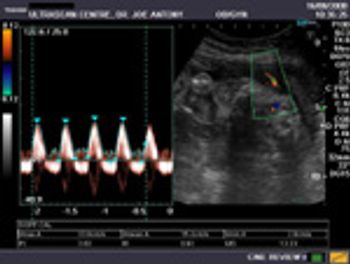

These are ultrasound images of an early pregnancy.